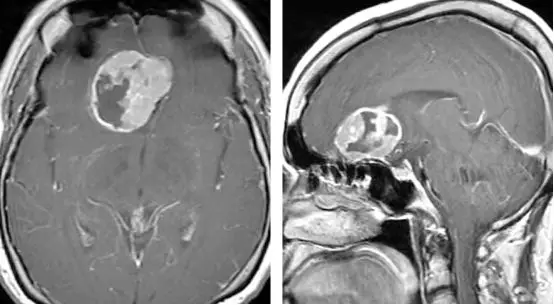

图15. 患者表现为思维混乱,检查提示为较大的嗅沟脑膜瘤伴周围水肿。

图16. 图为经右侧翼点入路的术中示意图。第一张图展示了肿瘤后极与周围神经血管结构的关系。额下外侧途径早期即可以辨认出肿瘤与其周围的视神经和颈内动脉。在保护视神经和颈内动脉的同时,对肿瘤基底切断血供(第二排)。肿瘤基底部血供被完全切断,直至对侧眶壁及对侧额下区的软膜完全暴露(第三排)。在肿瘤瘤内减压并分块切除后,将大脑前动脉及其分支从肿瘤后极上游离。